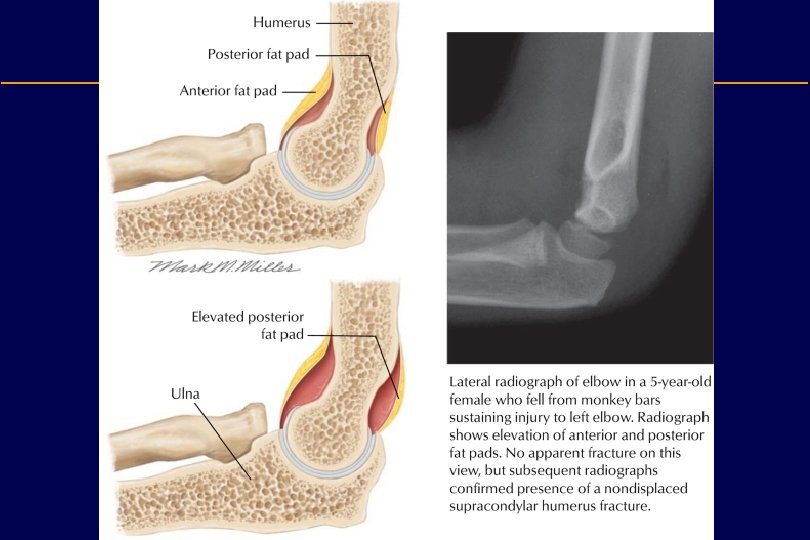

Distal Humerus • Coronoid fossa: – Accommodates the coronoid process of the ulna during flexion. – A fat pad is situated here • Radial fossa: – Accommodates the head of the radius during flexion. – A fat pad is situated here • Olecranon fossa: – Accommodates the olecranon – A fat pad is situated here • Groove for ulnar nerve

Supracondylar fractures • These fractures occur most commonly in children between the ages of 6 -9 years. • These fractures may lead to vascular and neurological complications